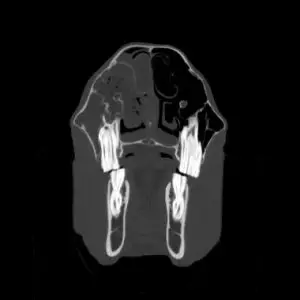

Die Computertomographie ist, ähnlich wie die Magnetresonanztomographie, ein Schnittbildverfahren. Anders als bei der MRT entstehen die CT-Bilder mit Hilfe von Röntgenstrahlen. Dabei wird das Pferd schichtweise durchleuchtet, und aus den zahlreichen Einzelaufnahmen errechnet ein Computer ein dreidimensionales Bild der untersuchten Region. So lassen sich selbst sehr kleine Veränderungen an Knochen oder Weichteilen sichtbar machen, die mit klassischen Röntgenbildern nicht erkennbar wären. Bei Bedarf kann zusätzlich ein Kontrastmittel eingesetzt werden, um bestimmte Strukturen noch besser darzustellen.

Ein besonderer Vorteil unseres Systems ist die Möglichkeit, viele Untersuchungen am stehenden, sedierten Pferd durchzuführen. Dank einer Grube, in der sich das CT-Gerät nicht nur vor- und zurück-, sondern auch auf- und abwärts bewegen kann, lassen sich Kopf, Teile der Halswirbelsäule und die unteren Gliedmaßen (bis zum Vorderfußwurzel- bzw. Sprunggelenk) ohne Vollnarkose untersuchen. Das reduziert das Risiko für das Pferd und ermöglicht einen schonenderen Ablauf.